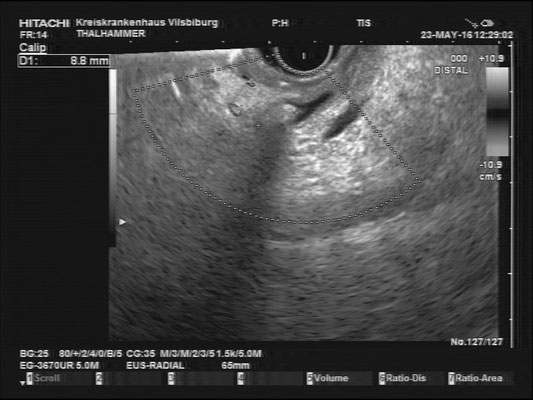

Pancreas

The images above depict a thorough inspection of the pancreas, as seen in an radial EUS Examination. We begin (hopefully ;) bei identifying the uncinate process between the golden V, which is formed by the aorta/V. cava and the mesenteric vessels. After spotting die usually hypoechoic ventral pancreatic root, the duodenal papilla can be identified (for a more detailed approach, please visit "Learning Endosono"). By following the splenic vein, the body and tail of the pancreas can be examined.

The most observant viewers will have noticed that not all images above depict normal findings but some abnormalities. (my bad ;)